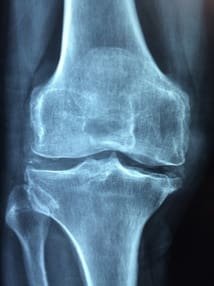

Gonarthrose, quoi de neuf ce mois-ci ?

Un essai clinique a voulu tester l’efficacité d’un programme d’exercices versus un traitement pharmacologique sur les activités de la vie quotidienne (AVQ) chez des patients avec une gonarthrose (atteinte légère à modérée).